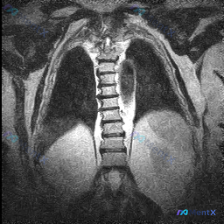

影像报「胸椎形态基本规整对称」,但高度怀疑脊柱侧弯?问题可能出在哪?

背景是临床高度关注「脊柱侧弯」的问题,但拿到的单幅胸部MRI冠状位报告是这么写的:

- 胸椎序列在可视范围内形态基本规整

- 两侧肋骨形态对称,纵隔居中

- 未见明显椎体骨质破坏或压缩骨折

- 肺野、胸膜、纵隔、膈肌也都没报明显异常

简单说就是——从这张图上,看不到符合临床定义的脊柱侧弯典型征象。

但问题来了:如果临床确实高度怀疑侧弯,这时候能直接排除吗?还是应该先考虑哪些「干扰因素」?